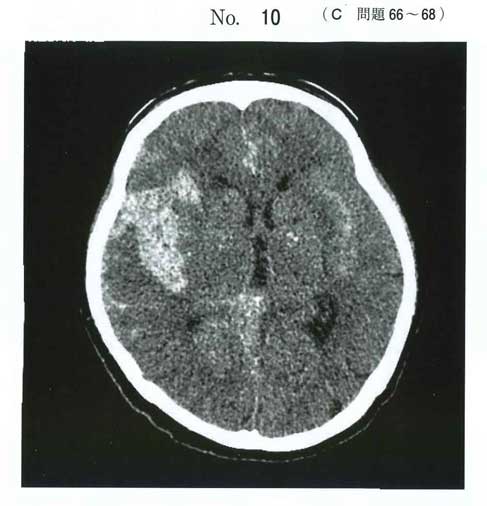

| タイトル:117C-66 | コメント数:4 |

eは禁忌になる可能性あり(明らかなSAHなので)

ニトロはCS1の心不全以外あまり使わない気がします。降圧は基本は二カルジピンです

ニトロはどうなんでしょうね…。